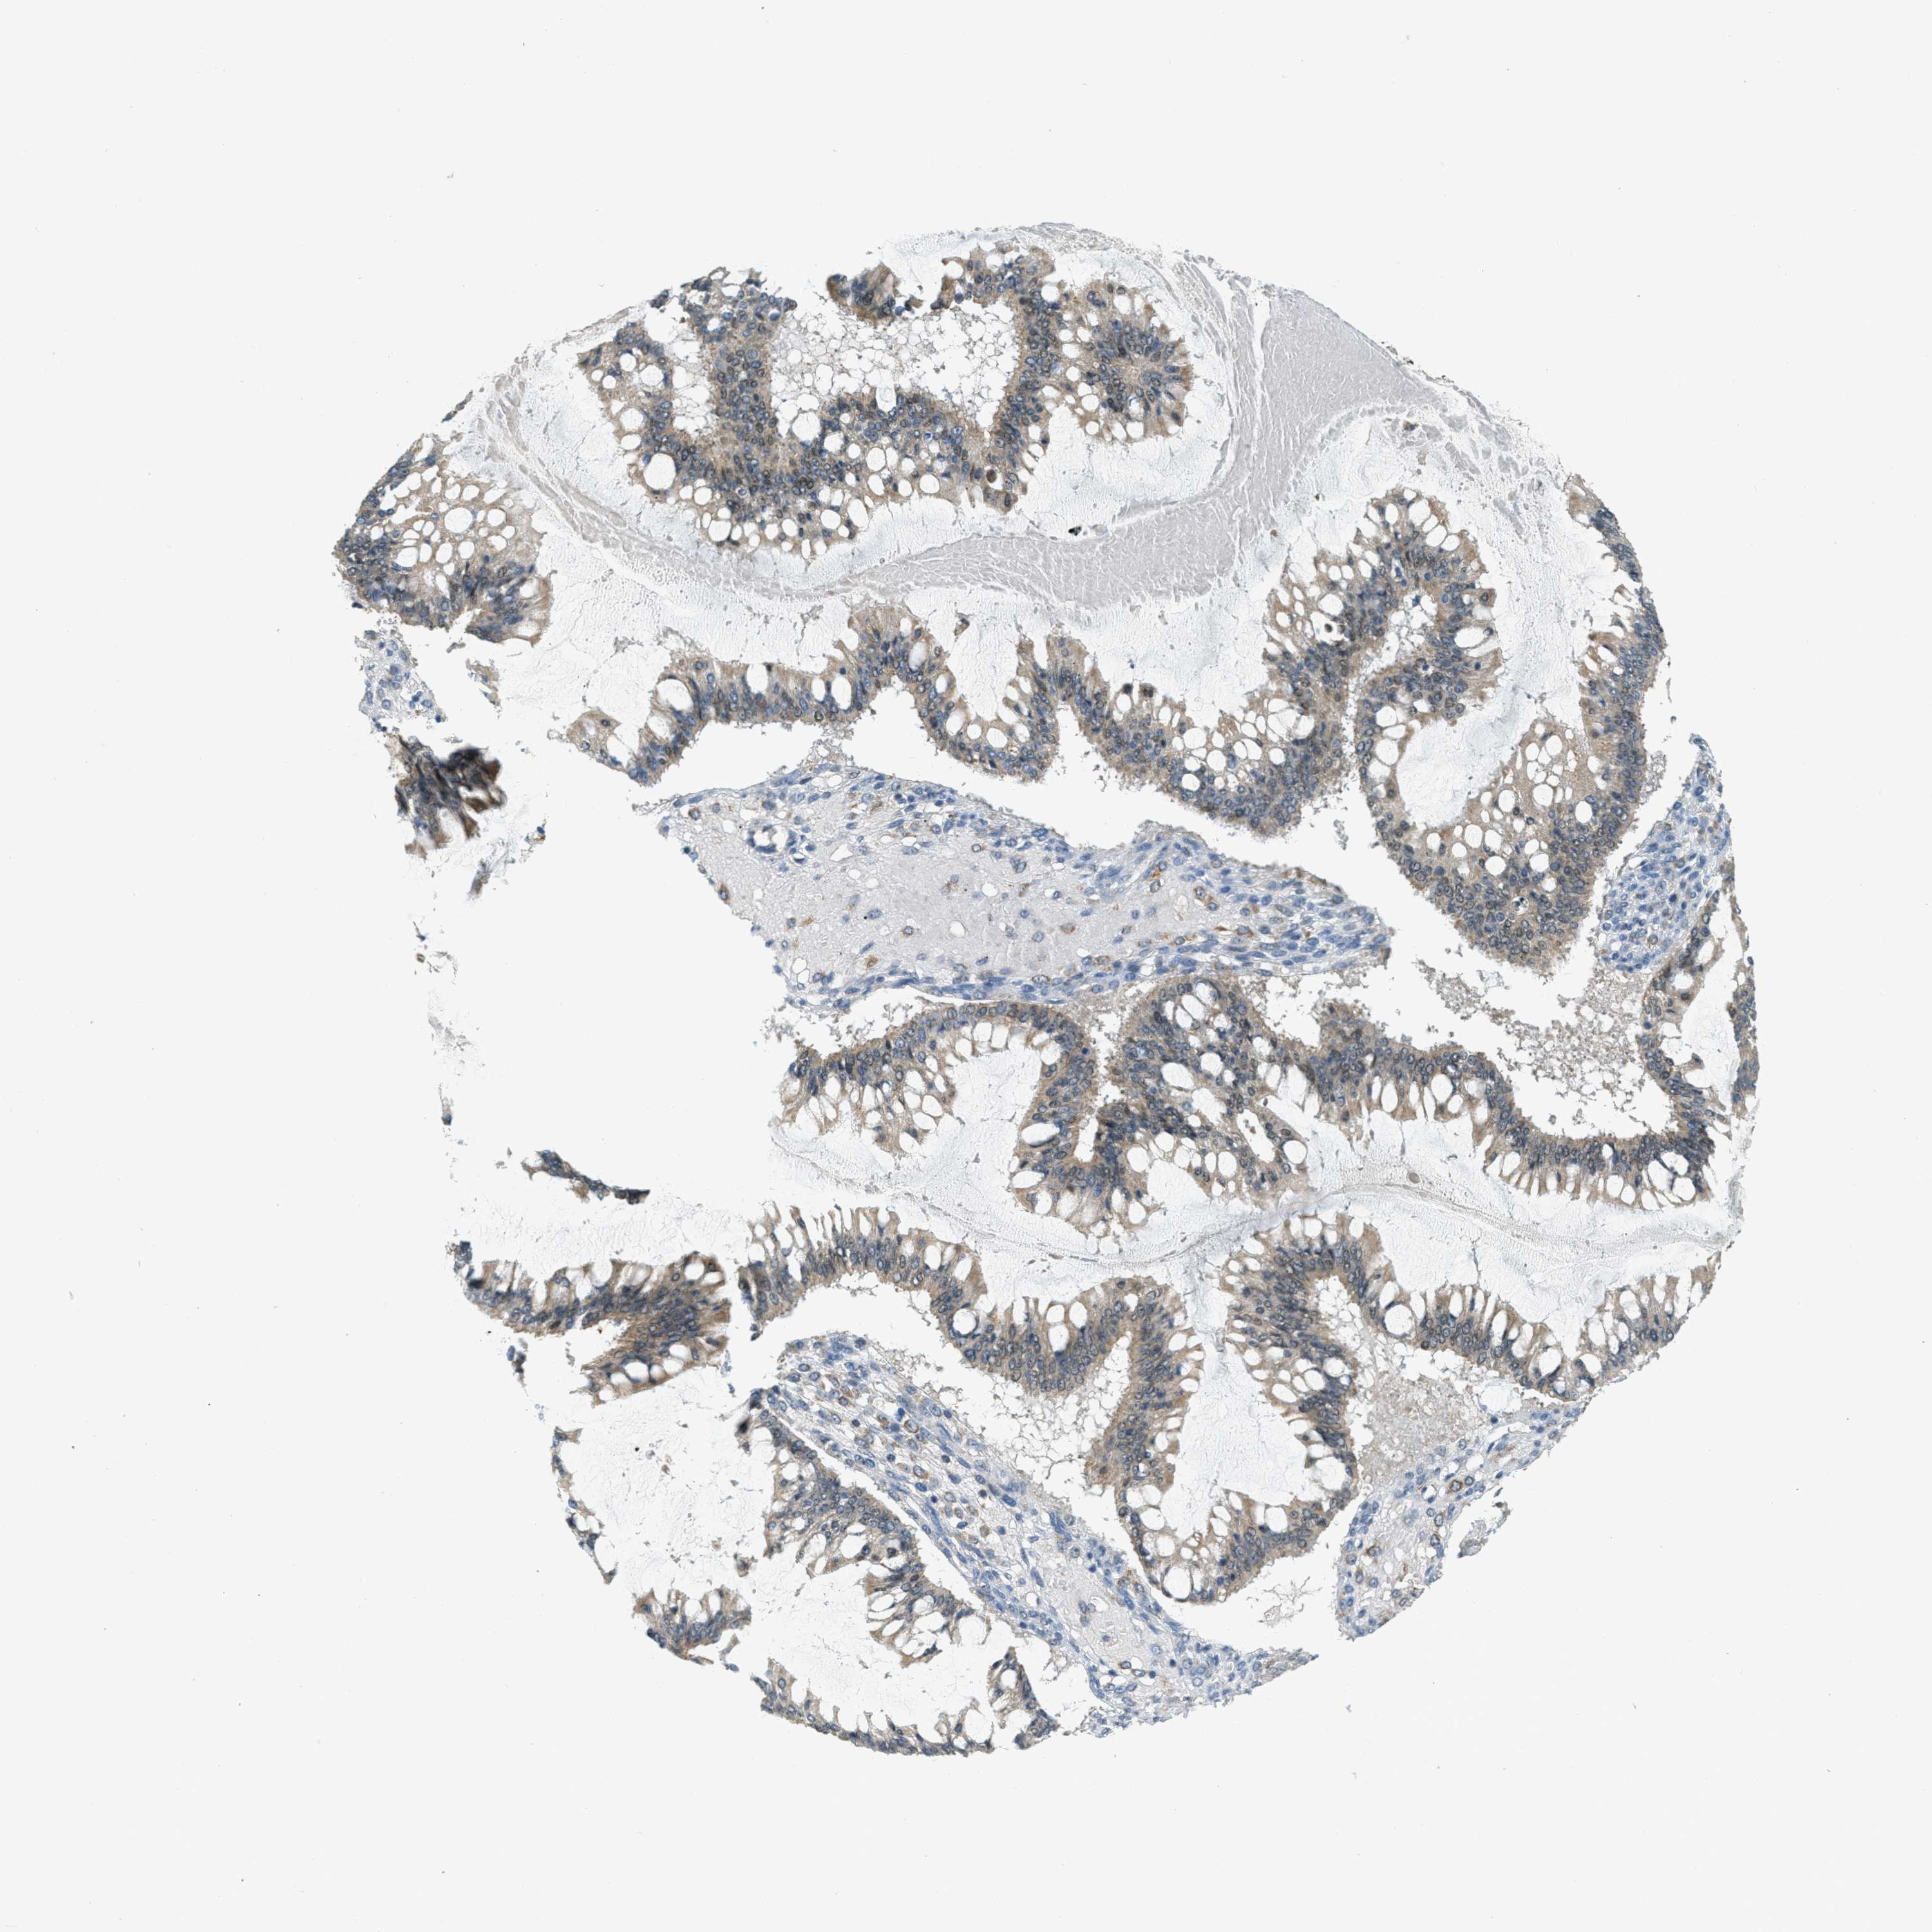

OVARIAN CANCER - Protein expressioni

A mouse-over function shows sample information and annotation data. Click on an image to view it in a full screen mode. Samples can be filtered based on level of antibody staining by selecting one or several of the following categories: high, medium, low and not detected. The assay and annotation is described here.

Note that samples used for immunohistochemistry by the Human Protein Atlas do not correspond to samples in the TCGA dataset.

Antibody stainingi

Antibody staining in the annotated cell types in the current human tissue is reported as not detected, low, medium, or high, based on conventional immunohistochemistry profiling in selected tissues. This score is based on the combination of the staining intensity and fraction of stained cells.

Each image is clickable and will lead to virtual microscopy that enables deeper exploration of all samples and also displays staining intensity scores, fraction scores and subcellular localization as well as patient and tissue information for each sample.

Antibody HPA036786

Antibody CAB017849

Carcinoma, NOS

Cystadenocarcinoma, serous, NOS